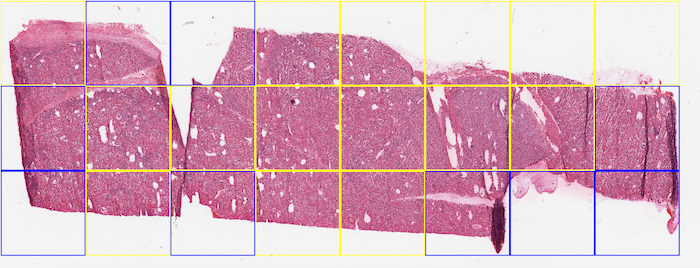

To evaluate the generalization and the practical performance, we also selected five WSIs from the NIH dataset222https://gdc.cancer.gov. We selected WSIs from three different organs (kidney,lung and colon). Figure 3 shows two sample WSIs alongside the boundary boxes of our classifier.

Classifiers, which are trained on small datasets predominantly fail to generalize on new classification categories. In our experiments, we selected five new WSIs with a noticeable amount of folded tissue from the NIH dataset to evaluate the ability of deep features and SVM to generalize to unseen cases. We applied our method in different window sizes with no overlap. All patches will be resized to before feeding to the network. Figure 3 shows sample WSIs from NIH database with different window sizes. Blue boxes are representative of the presence of folded tissue while a yellow box represents normal tissue. The overall accuracy in generalization test set with pixel size dropped to . A possible explanation for this result may be the lack of adequate fold pattern samples in the training set. Besides the difference in an organ type, scanner brand should also be considered. However, as we trained and tested the classifiers for patch-wise tissue detection, one has to bear in mind that the detection of one tissue fold is sufficient to flag a scan for visual inspection.

It can be seen in Figure 3(b) that there is a folded patch which has not been detected. There might be some justifications for this false negative -yellow window in Figure 3 (b)-. The first one is that our training dataset enclosed the entire folded tissue within each patch (i.e., no folded tissue was split between two patches). In this false negative example, however, the patch does not contain all of the folded tissue, and parts of the folded tissue are contained within the neighbouring patches. The same error has occurred in Figure 3(c). The second justification is that the training patch sizes were about 5000 by 5000 pixels, while the experiment window size was 1500 by 1500, therefore training with bigger size patches (patch in lower magnification) might have been the reason for false negatives.